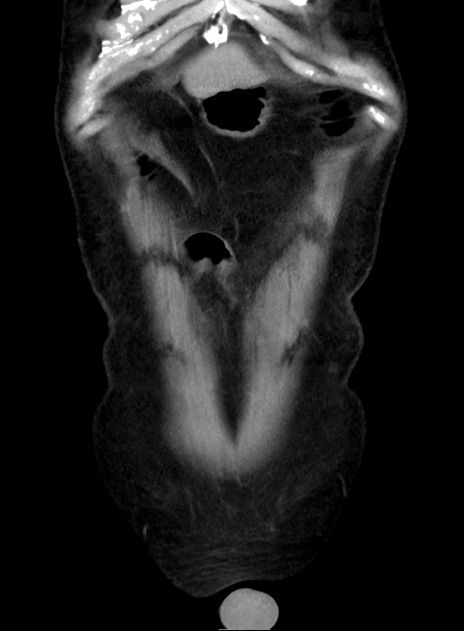

症例38(冠状断像)

【症例】70歳代 男性

【主訴】腹痛・嘔吐

【現病歴】昨晩より、嘔吐・腹痛あり。今朝になっても嘔吐あり。来院。

【既往歴】心臓バイパス手術、開腹胆摘、腸閉塞

【身体所見】BP 107/71mmHg、HR 116/min、腹部:平坦、軟、下腹部に軽度圧痛あり。反跳痛なし。

【データ】WBC 15100、CRP 0.32